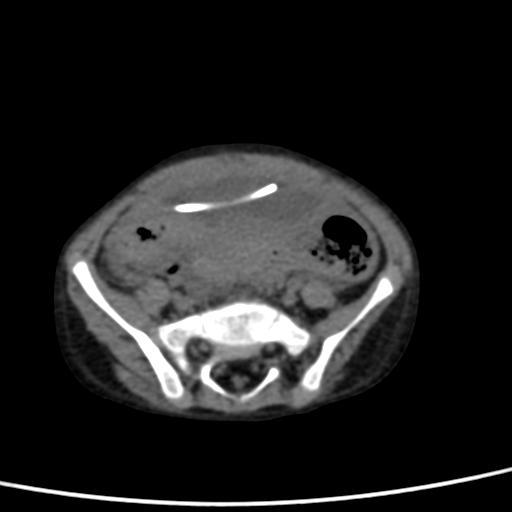

Viene dunque sottoposto ad una TC encefalo che esclude segni di idrocefalo iperteso e a una ecografia e una TC addominale che mostrano la presenza di una formazione cistica plurisettata di circa 7 x 5 x 3 cm all�estremit� distale del sistema di derivazione, riferibile a raccolta liquorale (Figura 1).

Figura 1. TC assiale: formazione cistica ovalare in sede sovravescicale contenente l�estremit� distale del catetere.